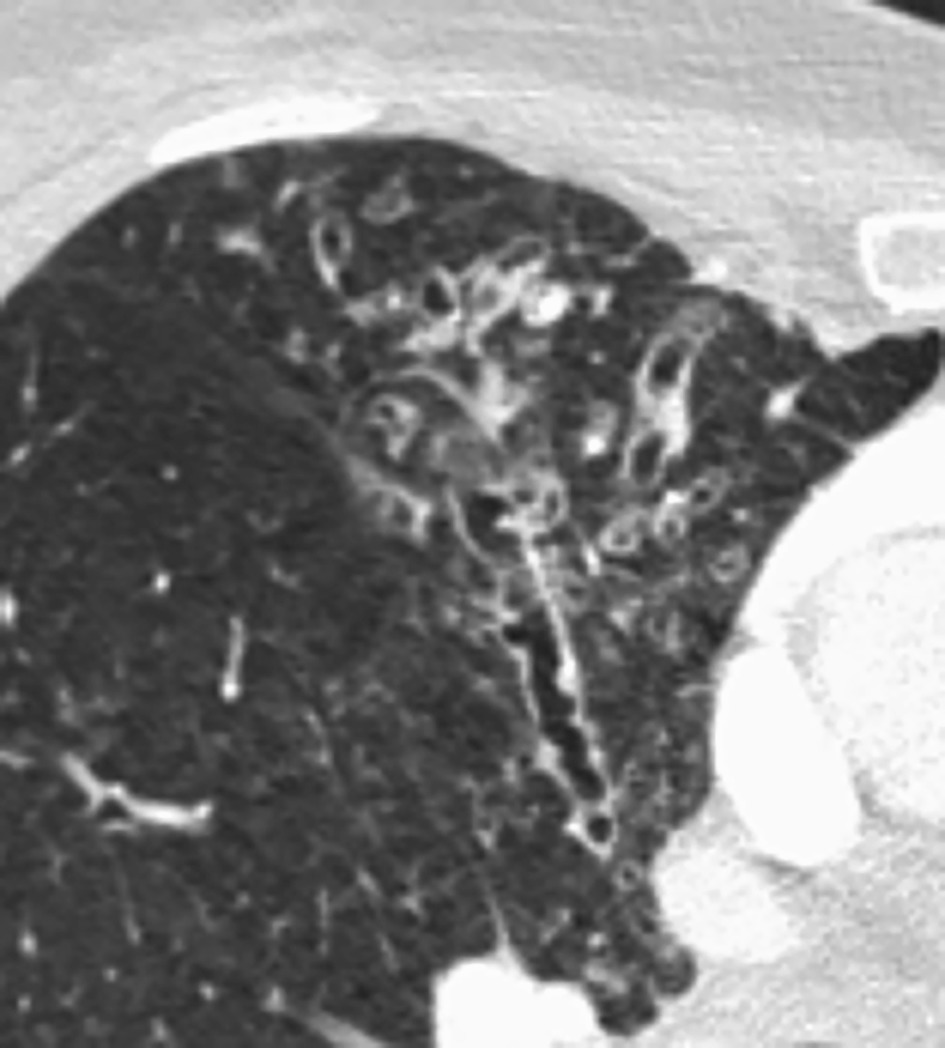

Seul un scanner thoracique haute résolution confirme le diagnostic anatomique : augmentation permanente et irréversible du calibre des bronches sous-segmentaires, cylindriques, variqueuses ou kystiques, localisées à un lobe ou diffuses. On élimine une autre cause de toux chronique comme un cancer bronchique. Toux, expectoration, infections bronchiques répétées + bronchectasies au scanner définissent le syndrome bronchectasique.